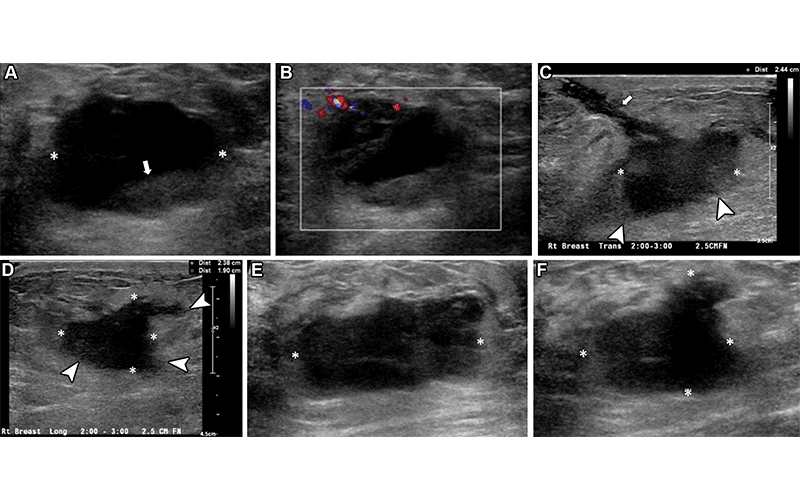

Right breast palpable lump and pain in a 37-year-old woman who was evaluated in the ED. (A, B) Initial gray-scale (A) and color Doppler (B) US images show an oval, hypoechoic to anechoic lesion (* in A) in the right breast, which appeared to have a fluid-fluid level (arrow in A) and some peripheral vascularity detected (B). An abscess was suspected, and needle aspiration without imaging guidance was attempted in the ED. However, no obvious aspirate was obtained. The patient was managed clinically with antibiotics; however, she returned to the ED 1 month later owing to persisting pain and new serosanguineous drainage through the skin. (C, D) Orthogonal US images obtained at the second visit had a better gain adjustment, showing the mass (*) with additional features such as an irregular shape and indistinct margins (arrowheads). A tract (arrow in C) toward the skin in the region of active drainage was observed. (E, F) US images obtained at recommended urgent complete assessment in the breast imaging department show a solid, irregular hypoechoic mass (*) with angular and indistinct margins at the site of concern. Biopsy revealed triple-negative invasive ductal carcinoma. https://pubs.rsna.org/doi/10.1148/rg.230020 ©RSNA 2023